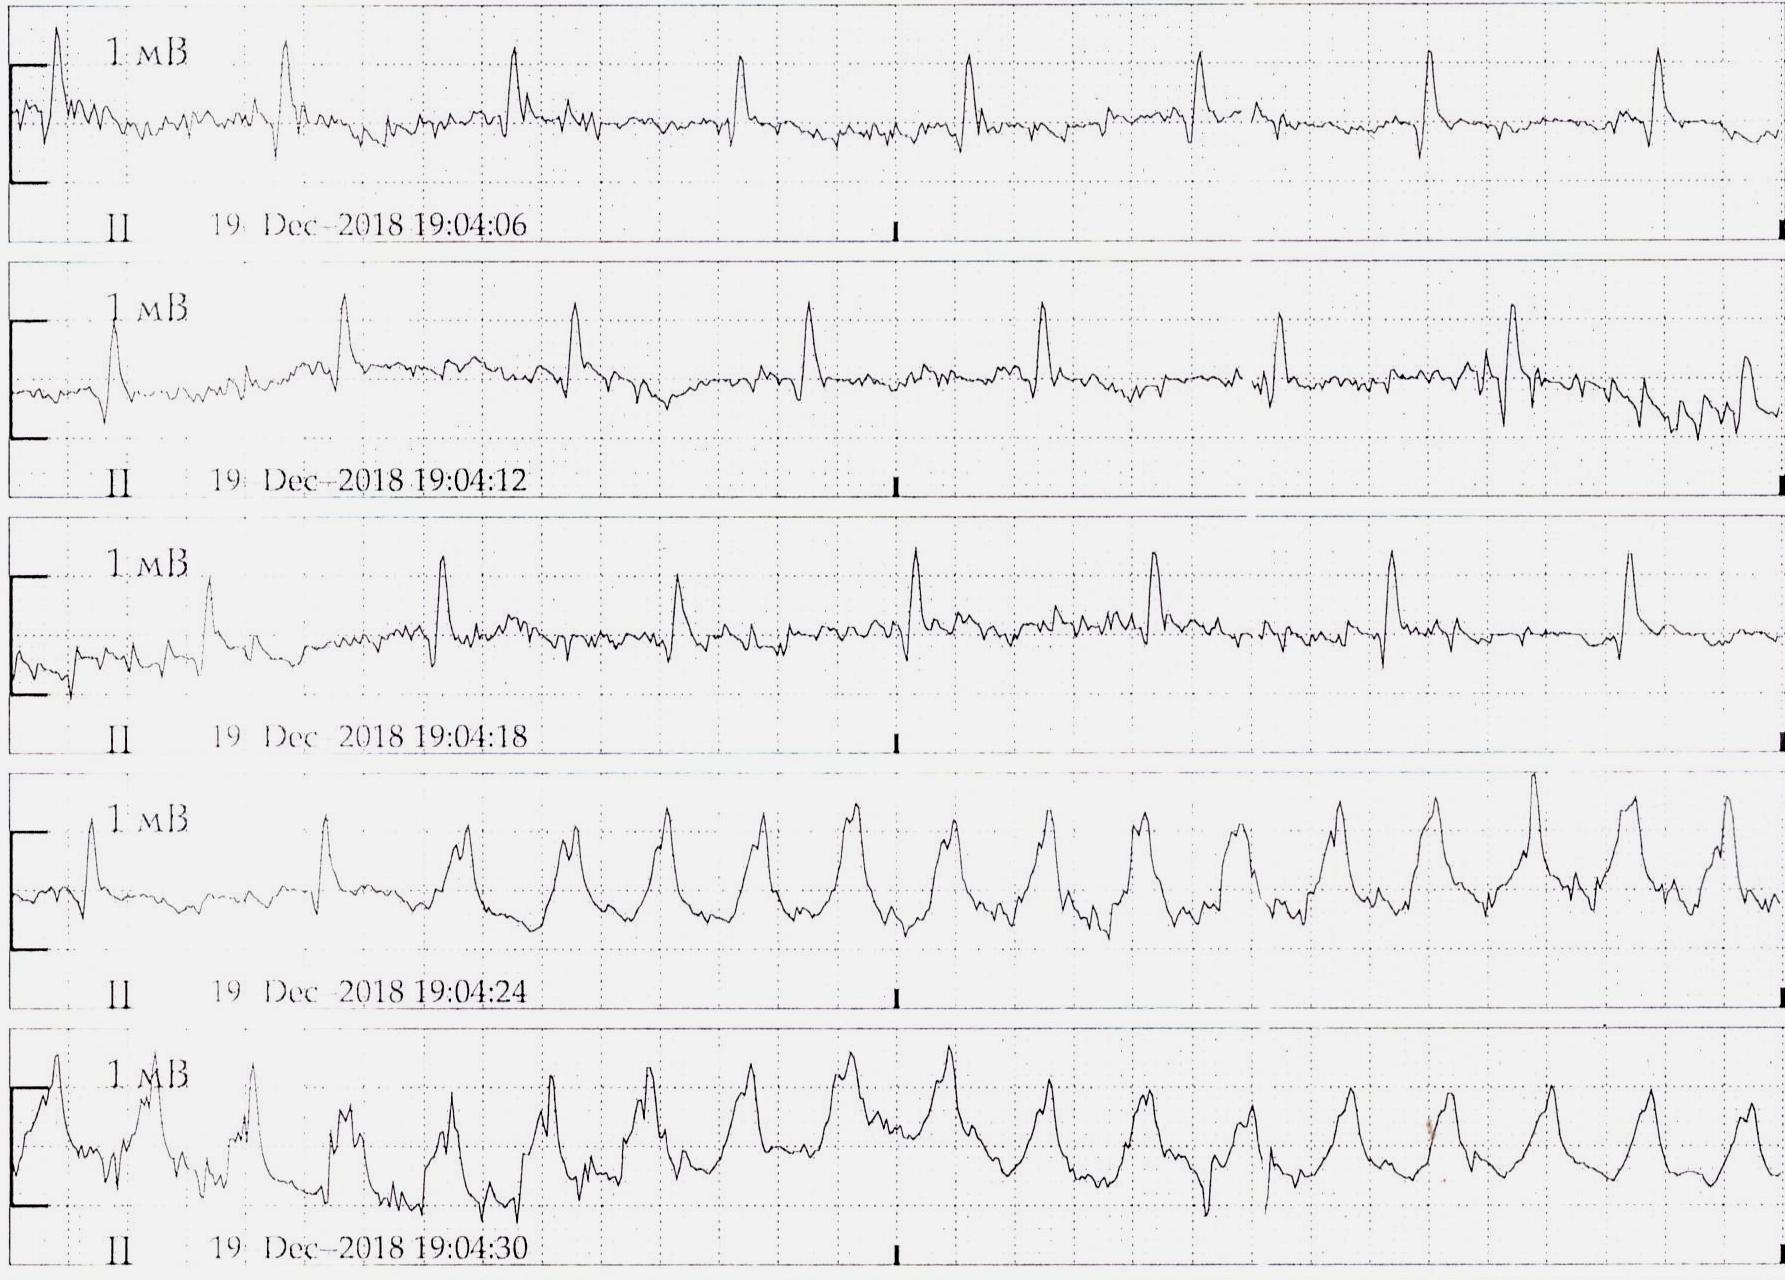

Пируэтная, хоть и пируэт не классический

Вложения:

1.jpg

1.jpg [ 263.14 KiB | Просмотров: 36863 ]

2.jpg

2.jpg [ 241.86 KiB | Просмотров: 36863 ]